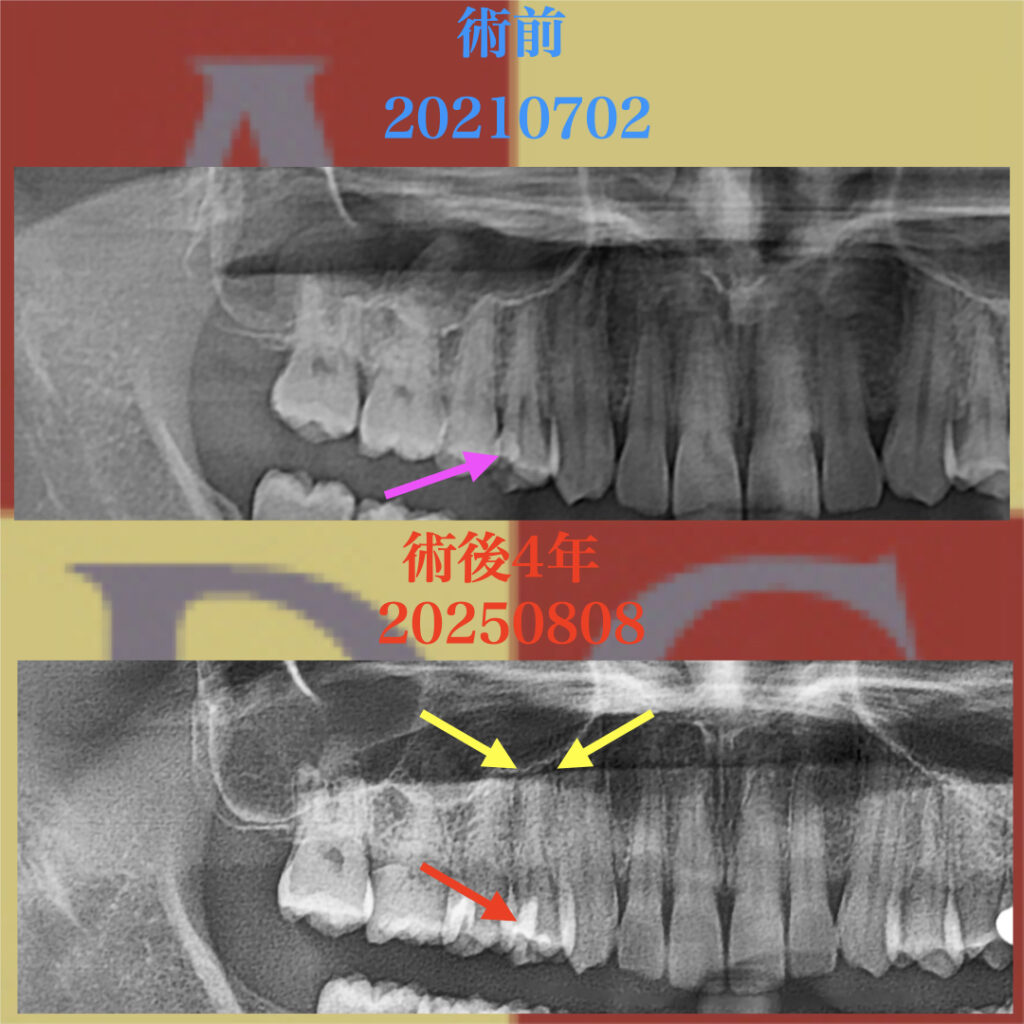

1年後のメインテナンス中のパノラマX線写真

歯髄に達するMTAセメントが確認できるが、

歯根膜腔の連続性を確認し、壊死後に現れる歯根膜腔の拡大が見られない。

術後4年経過のパノラマX線写真

黄色の矢印の部分に歯根膜腔の連続性が確認できる

術前に見られた歯根膜の連続性が、術後も確認できる。

隣接する歯の歯髄よりも深い部分にまでMTAセメントが確認できる